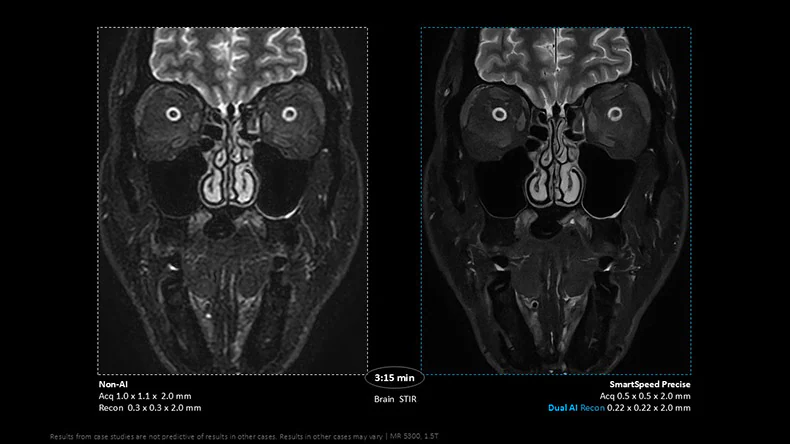

Integrated Dual AI: A breakthrough in image reconstruction

SmartSpeed Precise combines three powerful technologies into one seamless solution which includes:

- Compressed SENSE, Philips’ gold-standard acceleration engine;

- An AI-powered denoising engine, enhancing image clarity by reducing noise; and

- A second AI engine for image sharpening and anti-ringing, ensuring exceptional definition and diagnostic quality.

The unique integrated dual AI approach sets SmartSpeed Precise apart in the industry. Technologists can now deliver high-quality exams at record speeds, using a single-click workflow that adapts to their preferred denoising settings. This ease of use makes the solution valuable for seasoned and less experienced staff – an essential advantage in today’s understaffed healthcare environments.

SmartSpeed Precise delivers a powerful combination of speed, precision, and simplicity that directly addresses the most urgent challenges facing radiology departments today. With scan times up to three times faster [2], providers can reduce patient backlogs by increasing throughput without compromising quality, reducing diagnostic scan times to levels not seen before, including a less than 10-second brain scan. The system delivers up to 80% sharper images [3], boosting diagnostic confidence in complex areas like neurology, oncology, and cardiology. Its streamlined, one-click workflow promotes consistent imaging across teams and patient anatomies, with easy protocol optimization ensuring reliable results, even in challenging cases like pediatric, elderly or uncooperative patients.